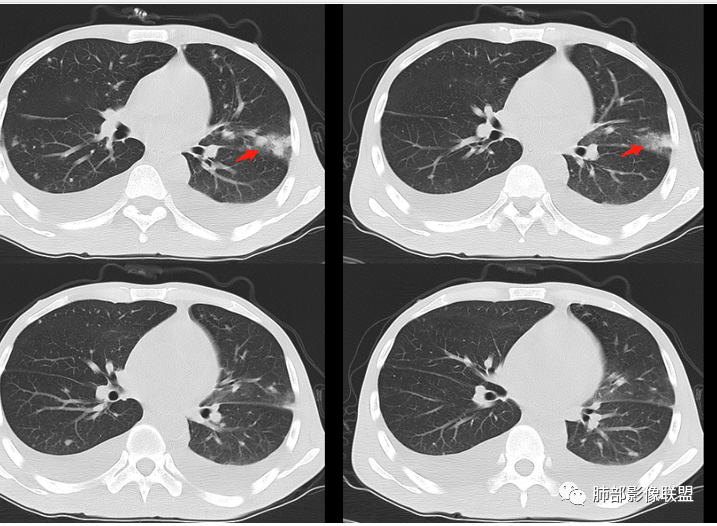

年轻男性,肠癌术后,目前间断有发热,胸部CT提示双肺散在结节影,左肺上叶近胸膜处可见以不规则密度增高影,边界不清,周边可见磨玻璃影,附近支气管壁增厚,支气管引流,附近可见卫星结节,内有空洞,考虑二元,转移瘤合并结核

青年男性,既往结肠癌病史,卡培他滨加贝伐单抗治疗,末次化疗时间2019年9月 有肠梗阻病史。低热,血常规基本正常低蛋白血症,血糖偏高,肾功能衰竭,CT提示双侧胸腔积液,双肺散在结节影,胸膜下多见,左上肺密度增高影,第一个选择我还是考虑感染。结核,真菌?第二恶性肿瘤,常规考虑转移。很好奇这病咋确诊

年轻患者恶性肿瘤术后,两分内,散在多发小结节状影,主要胸膜下及小叶核心分布,另外左肺上叶斑片状的模糊阴影,楔形。两侧胸腔积液及心包积液。肝脾弥漫性肿大,腹腔积液。肺部病灶考虑转移瘤合并有肺部的感染性病变。左心室见斑片状的低密度影,这个需要做个增强扫描看一下了。胸腔积液,心包积液,腹部少量积液,这个应该是多脏器的损害的改变,脾肝体积好像有增大,实质密度略有降低,也是损害的一种表现。建议全腹增强扫描。

青年男性,恶性肿瘤化疗病史,透析病史,血糖高,提示糖尿病。白细胞不高,伴发热,贫血,双侧胸腔积液,左肺上叶片状高密度影,边缘可见磨玻璃密度,临近支气管管壁增厚,内可见空泡,双肺另多发小结节,随机分布,部分结节周围有晕,一元解释,考虑感染性病变,真菌可能大

飞鹰行动:

青年男性,有恶性肿瘤化疗病史,血糖高。发热,贫血,双侧胸腔积液,左肺上叶片状高密度影,边缘可见磨玻璃密度,临近支气管管壁增厚,内可见空泡及小空洞,未见明显液平面,双肺另多发小结节,随机分布,部分结节周围有晕,考虑血道来源感染性病变,肺克,奴卡,大肠杆菌,真菌可能。

2.双肺散在不规则小片状影及结节影,部分可见磨玻璃晕。结节影边界较清楚。左肺片影边界不清,范围较大,支气管相关,支气管壁增厚不明显,病灶内见液化空洞。